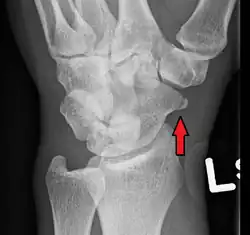

| An X-ray showing a fracture through the waist of the scaphoid | |